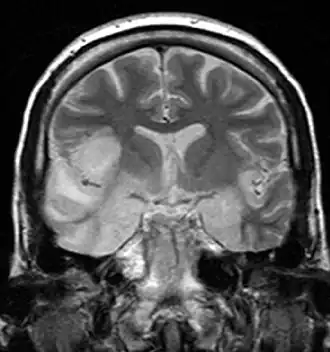

![]() Una IRM muestra una señal alta en los lóbulos temporales y la circunvolución frontal inferior derecha en un caso de encefalitis por HSV. | ||

Encefalitis límbica

La encefalitis límbica se refiere a la enfermedad inflamatoria confinada al sistema límbico del cerebro. La presentación clínica suele incluir desorientación, desinhibición, pérdida de memoria, convulsiones y anomalías del comportamiento. Las imágenes de IRM revelan hiperintensidad T2 en las estructuras de los lóbulos temporales mediales y, en algunos casos, en otras estructuras límbicas. Algunos casos de encefalitis límbica son de origen autoinmune.[16]